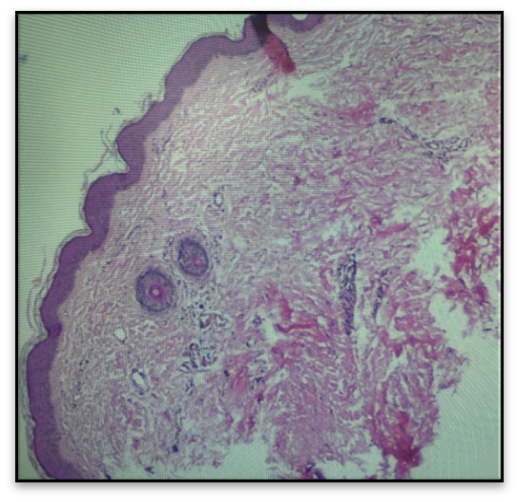

En ese contexto, se realizó una biopsia cutánea en la porción medial del miembro inferior izquierdo. El estudio histopatológico evidenció dermis esclerosada con engrosamiento de los haces de colágeno, hipocelularidad, disminución de anexos cutáneos y leve infiltrado linfoide, sin datos de actividad inflamatoria significativa, hallazgos compatibles con esclerodermia localizada profunda (morfea profunda) en fase crónica inactiva. (Figura 1 y 2)

Figura 1. Biopsia cutánea porción medial del miembro inferior izquierdo. Corte completo con marcada disminución de anexos cutáneos, folículos pilosos (hematoxilina-eosina, x10). Fuente:propia del autor.

Figura 2. Biopsia cutánea. (A)Dermis reticular compuesta por bandas gruesas de colágeno. (B). Presencia de escaso infiltrado linfocítico perivascular, sin signos de actividad inflamatoria significativa (hematoxilina-eosina). Fuente:propia del autor.

El caso presentado, con atrofia progresiva, induración cutánea y limitación funcional sin evidencia de compromiso sistémico, es coherente con estas características clínicas. El diagnóstico se establece mediante la correlación de hallazgos clínicos, histopatológicos y, en algunos casos, de imagen. Clínicamente, se observan placas, pérdida de tejido blando, atrofia y restricción funcional4. La histopatología muestra fibrosis de la dermis profunda y del tejido subcutáneo, con infiltrado inflamatorio variable según la fase de la enfermedad6. En esta paciente, la hipocelularidad, el engrosamiento de las bandas de colágeno y la evolución crónica sugieren una fase inactiva de la enfermedad.